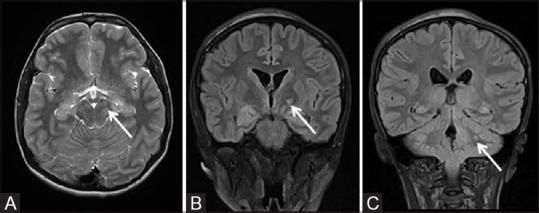

phakomatoses:图文综述。

Phakomatoses: A pictorial review.

Phakomatoses or Neurocutaneous syndromes are a heterogeneous group of disorders and have variable inheritance pattern. Currently, more than 30 entities are included in this group. These disorders primarily affect the central nervous system; however, skin, viscera, and other connective tissues can also be involved with variable clinical presentation. We will describe and illustrate the various radiological findings of the common entities through the iconography of the cases presented to our department.

摘要

phakomatoses或神经皮肤综合征是一组异质性疾病,具有可变的遗传模式。目前,该组包括30多种疾病。这些疾病主要影响中枢神经系统;然而,皮肤、内脏和其他结缔组织也可能受累,临床表现各异。我们将通过提交至我科病例的影像学表现来描述和说明常见疾病的各种放射学表现。